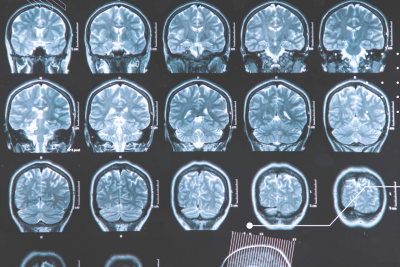

O tratamento geralmente é mais eficaz nos estágios iniciais da doença, por isso é essencial obter um diagnóstico o mais rápido possível. Além dos exames neurológicos (ressonância magnética, análise do líquido cefalorraquidiano, potenciais evocados), é essencial que o paciente detecte os sinais de alerta dados por seu próprio corpo.